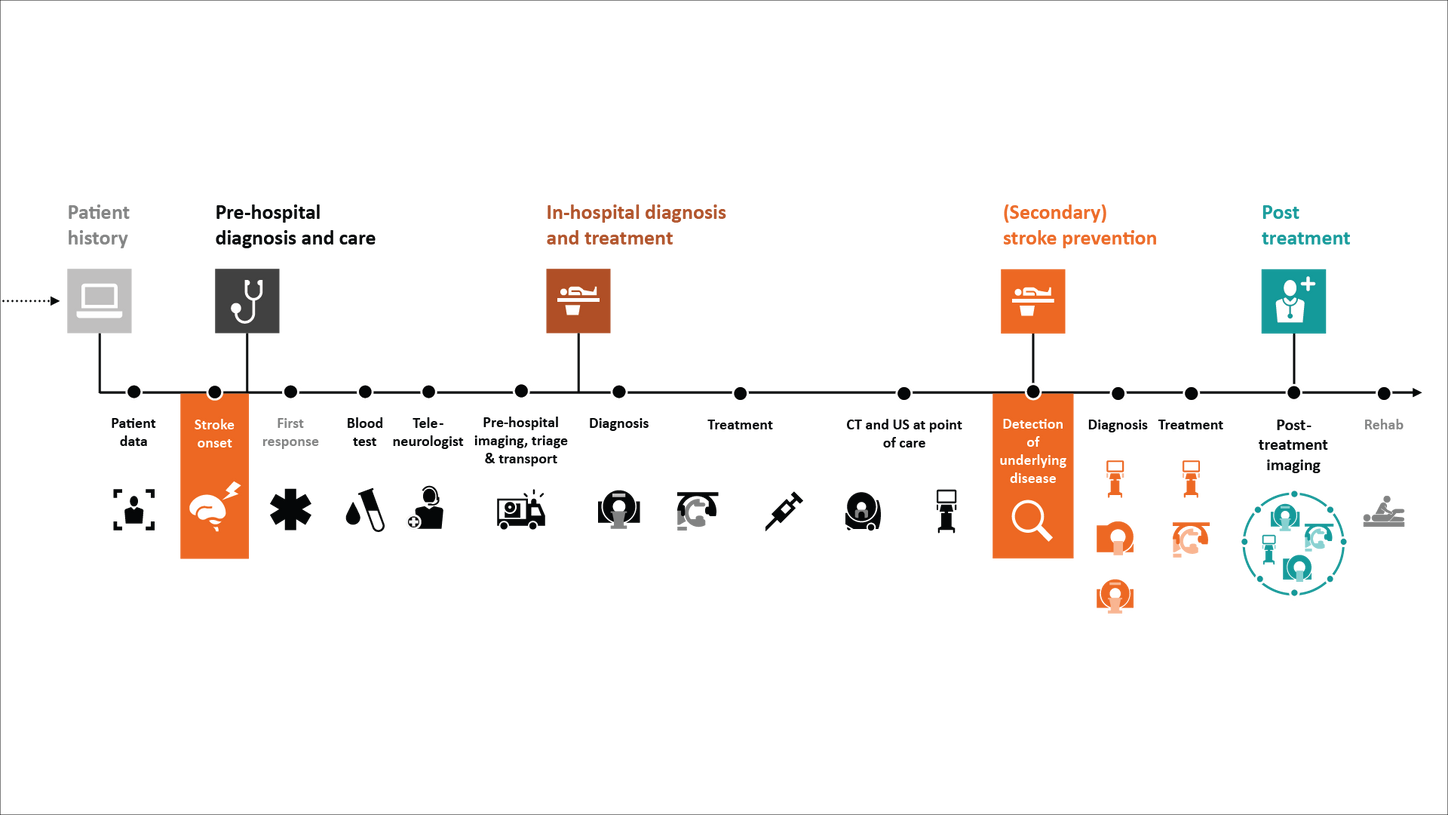

For stroke patients, time is of the essence. Every minute saved can positively impact patient outcomes.

That’s why it’s key to save time along the entire stroke pathway – from the onset of stroke to treatment and follow-up.

Stroke solutions

As your partner in stroke management, we keep you ahead of your time. Our advanced technologies let you speed up stroke care and transform care delivery along the entire pathway – from stroke screening and pre-hospital diagnosis and care to in-hospital diagnosis and treatment and (secondary) stroke prevention to follow-up imaging. Explore our offerings for stroke care!